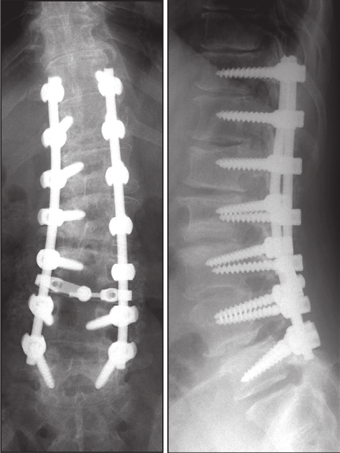

图5 脊柱远端融合节段越多,如包括L5-S1水平固定到骶骨或髂骨,发生交界性后凸的可能性越大

图6 长节段融合固定上固定椎(UIV)选择在胸10-12胸腰椎交界区是PJK的风险因素之一